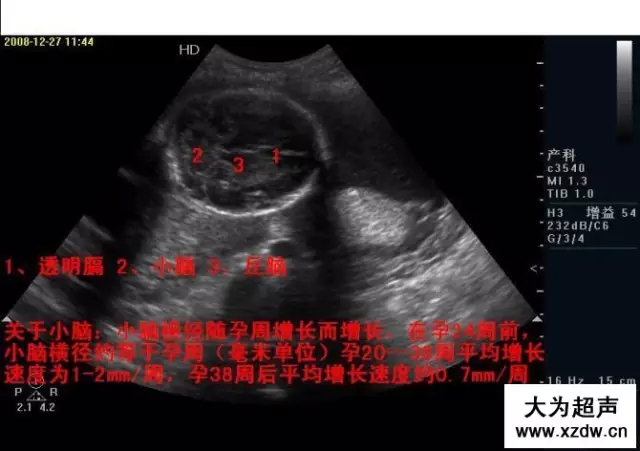

產科超聲正常圖片